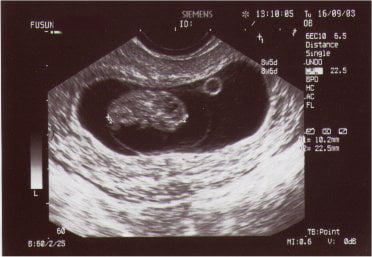

Yukarıdaki resimde 8 hafta 5 günlük bir gebelikte yolk kesesi

embryo ve amniyon zarı net bir sekilde görülmekte

Gestasyonel kese ortaya çıktıktan kısa bir süre sonra yolk kesesi (yolk sac) adı verilen oluşum ortaya çıkar. Yolk sac gestasyonel kese içinde ikinci ve daha küçük bir kese olarak gebeliğin yaklaşık 5. haftasında izlenebilir.

Gestasyonel kese çapı transvajinal ultrasonografide 10 milimetreye ulaştığında yolk kesesi izlenmelidir. Bu oluşumun izlenmesi gebeliğin normal olduğu şeklinde yorumlanır. Yolk kesesinin izlenmesi gebeliğin içinde embryo içermeyen boş gebelik olmadığını kanıtlar.

**Yolk kesesinin izlenmesinden çok kısa bir süre sonra bu kesenin alt kenarında bir kalınlaşma şeklinde embryo görülmeye başlar. Bu oluşuma fetal kutup (fetal pol, fetal pole) adı verilir. Uzunluğu yaklaşık 2-4 milimetredir ve 5.7-6.1 gebelik haftasına denk gelir.

Gestasyonel kese çapı 16-18 milimetreye ulaştığında embryo görülebilir hale gelir.